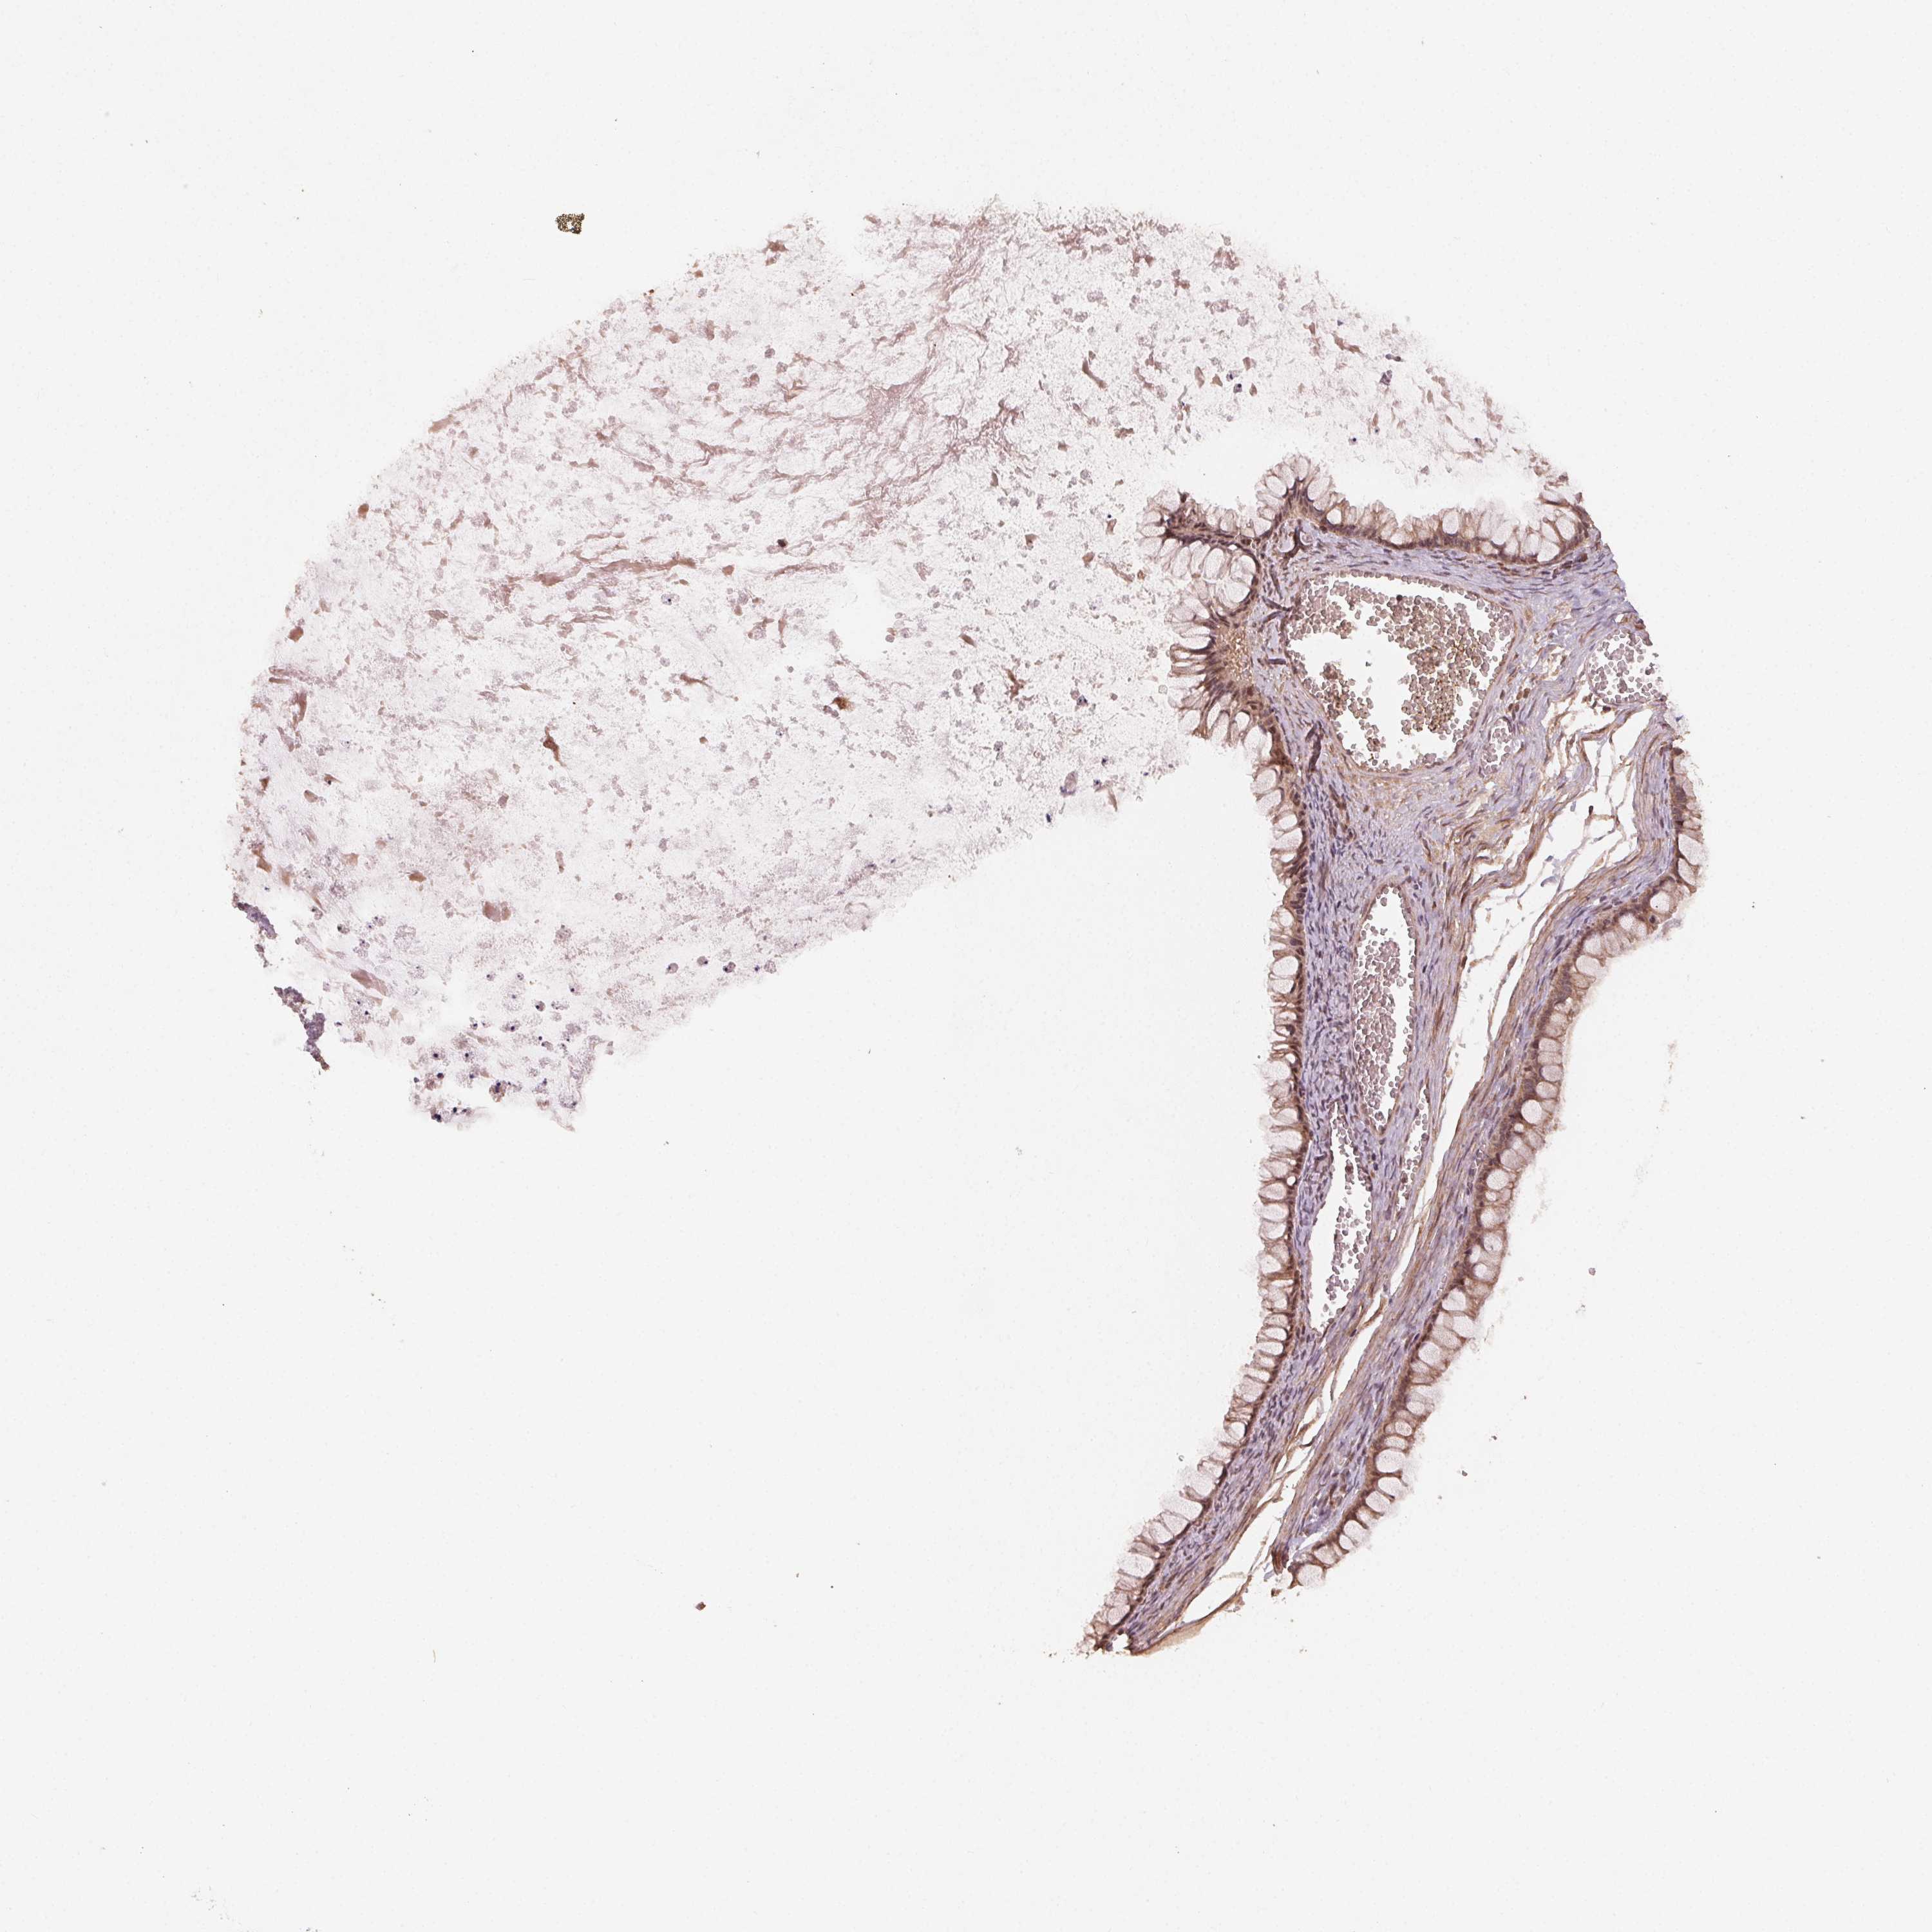

OVARIAN CANCER - Protein expressioni

A mouse-over function shows sample information and annotation data. Click on an image to view it in a full screen mode. Samples can be filtered based on level of antibody staining by selecting one or several of the following categories: high, medium, low and not detected. The assay and annotation is described here.

Note that samples used for immunohistochemistry by the Human Protein Atlas do not correspond to samples in the TCGA dataset.

Antibody stainingi

Antibody staining in the annotated cell types in the current human tissue is reported as not detected, low, medium, or high, based on conventional immunohistochemistry profiling in selected tissues. This score is based on the combination of the staining intensity and fraction of stained cells.

Each image is clickable and will lead to virtual microscopy that enables deeper exploration of all samples and also displays staining intensity scores, fraction scores and subcellular localization as well as patient and tissue information for each sample.

Antibody HPA065682

Staining

High

Medium

Low

Not detected

Intensity

Strong

Moderate

Weak

Negative

Quantity

>75%

75%-25%

<25%

None

Location

Nuclear

Cytoplasmic/membranous

Cytoplasmic/membranous,nuclear

Cystadenocarcinoma, serous, NOS

Cystadenocarcinoma, mucinous, NOS

Carcinoma, endometroid